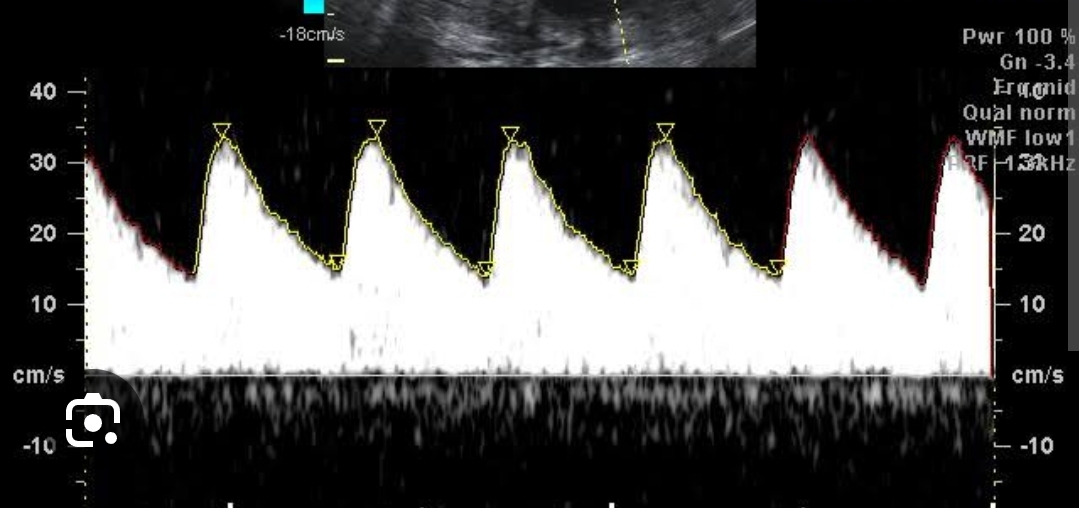

O que analisa o doppler de arteria umbilical? E o que se espera ao longo do tempo do doppler?

A circulação placentaria , e que a RP caia conforme o passar da gestação, visto no exame como a diatole se aproximando da sistole.

Q

O que fazer quando doppler de arteria umbilical diminuido ,mas não zero, e qual parâmetro estipula isso?

Parâmetro: S/D da umbilical em 35 sem > 3,5

Conduta: repetir doppler em 2 sem e se manteve igual parto em 37 sem